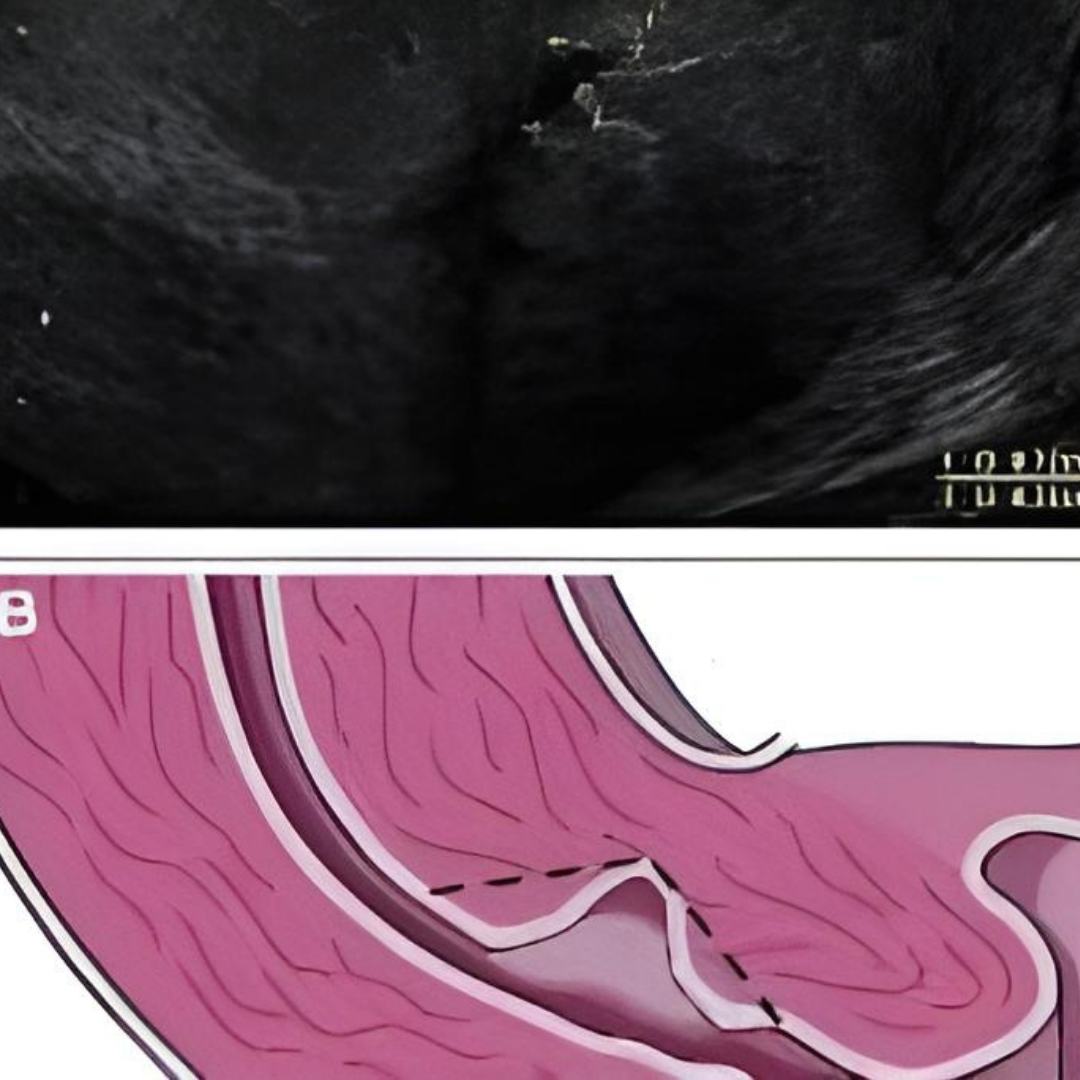

Ultrasonografi: Fetüsün gelişimi, organları, amniyotik sıvı miktarı ve plasenta durumu ultrasonografi ile incelenir.

Doppler Ultrasonografi: Fetüsün kan akışı ve kalp atışları değerlendirilir.

Biyofizik Profil: Ultrason ve nonstres testi ile fetüsün genel sağlığı, hareketleri, tonusu ve solunum hareketleri değerlendirilir.